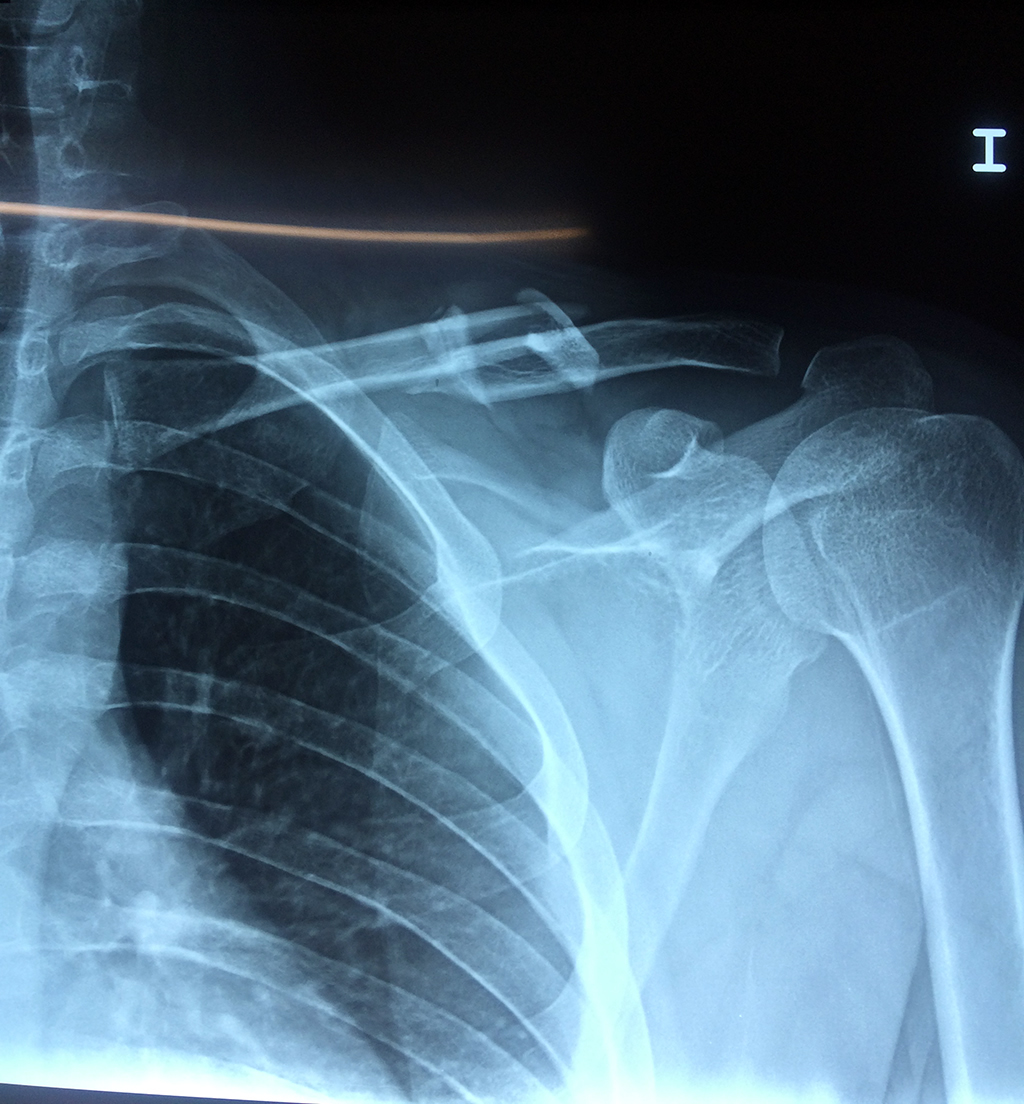

Cirugías de Húmero - Clavícula

La clavícula es un hueso largo, con forma de "S" itálica, situado en la parte anterosuperior del tórax. Junto con la escápula forman la cintura escapular. Se puede palpar por toda su longitud y se extiende del esternón al acromion de la escápula, siguiendo una dirección oblicua lateral y posterior.